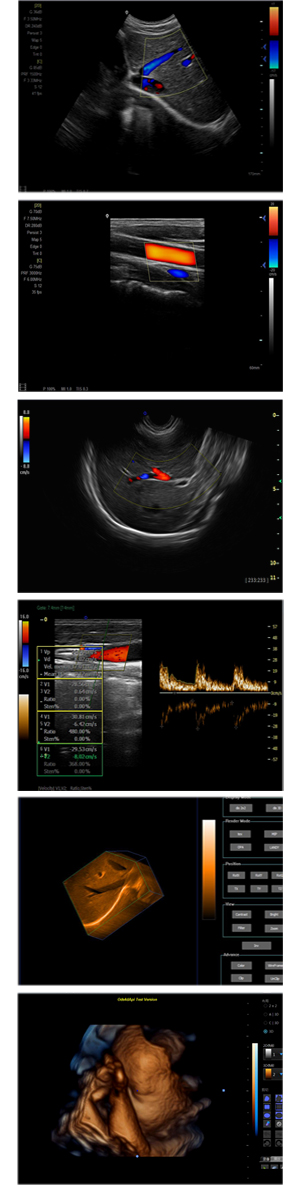

XF-7800型,秉承先鋒彩超技術之精華,擁有高雅大氣的獨特外型,為最新一代應用型數字彩色多普勒診斷系統,魅力與實力相融合。可廣泛適用于腹部、婦產科、心臟、小器官、乳腺、肌骨及外周血管等諸多方面的診查,讓您在臨床超聲診斷應用領域得心應手,綻放異彩!

● 3D/ 4D成像技術/限7800選配

● 應用于腹部、腎臟、泌尿系統、產科、婦科、盆腔、大動脈、肌肉組織、小器官、乳腺、心臟等

● 能量多普勒成像(PDI)

● 彩色血流量圖(CDE)

● 脈沖頻譜多普勒成像(PW)